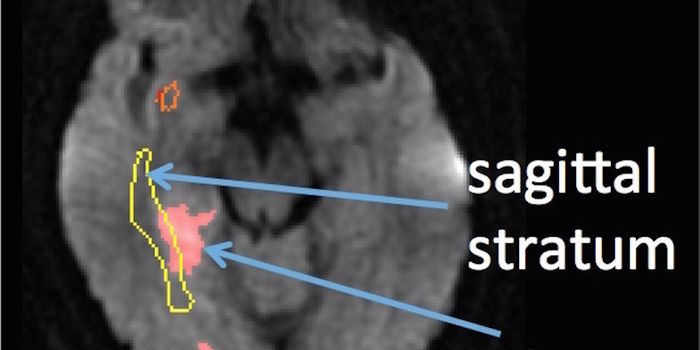

DEC 03, 2018NeuroscienceIdentifying the connection between the brain size to smartness has become much more plausible due to accuracy in estimat ...